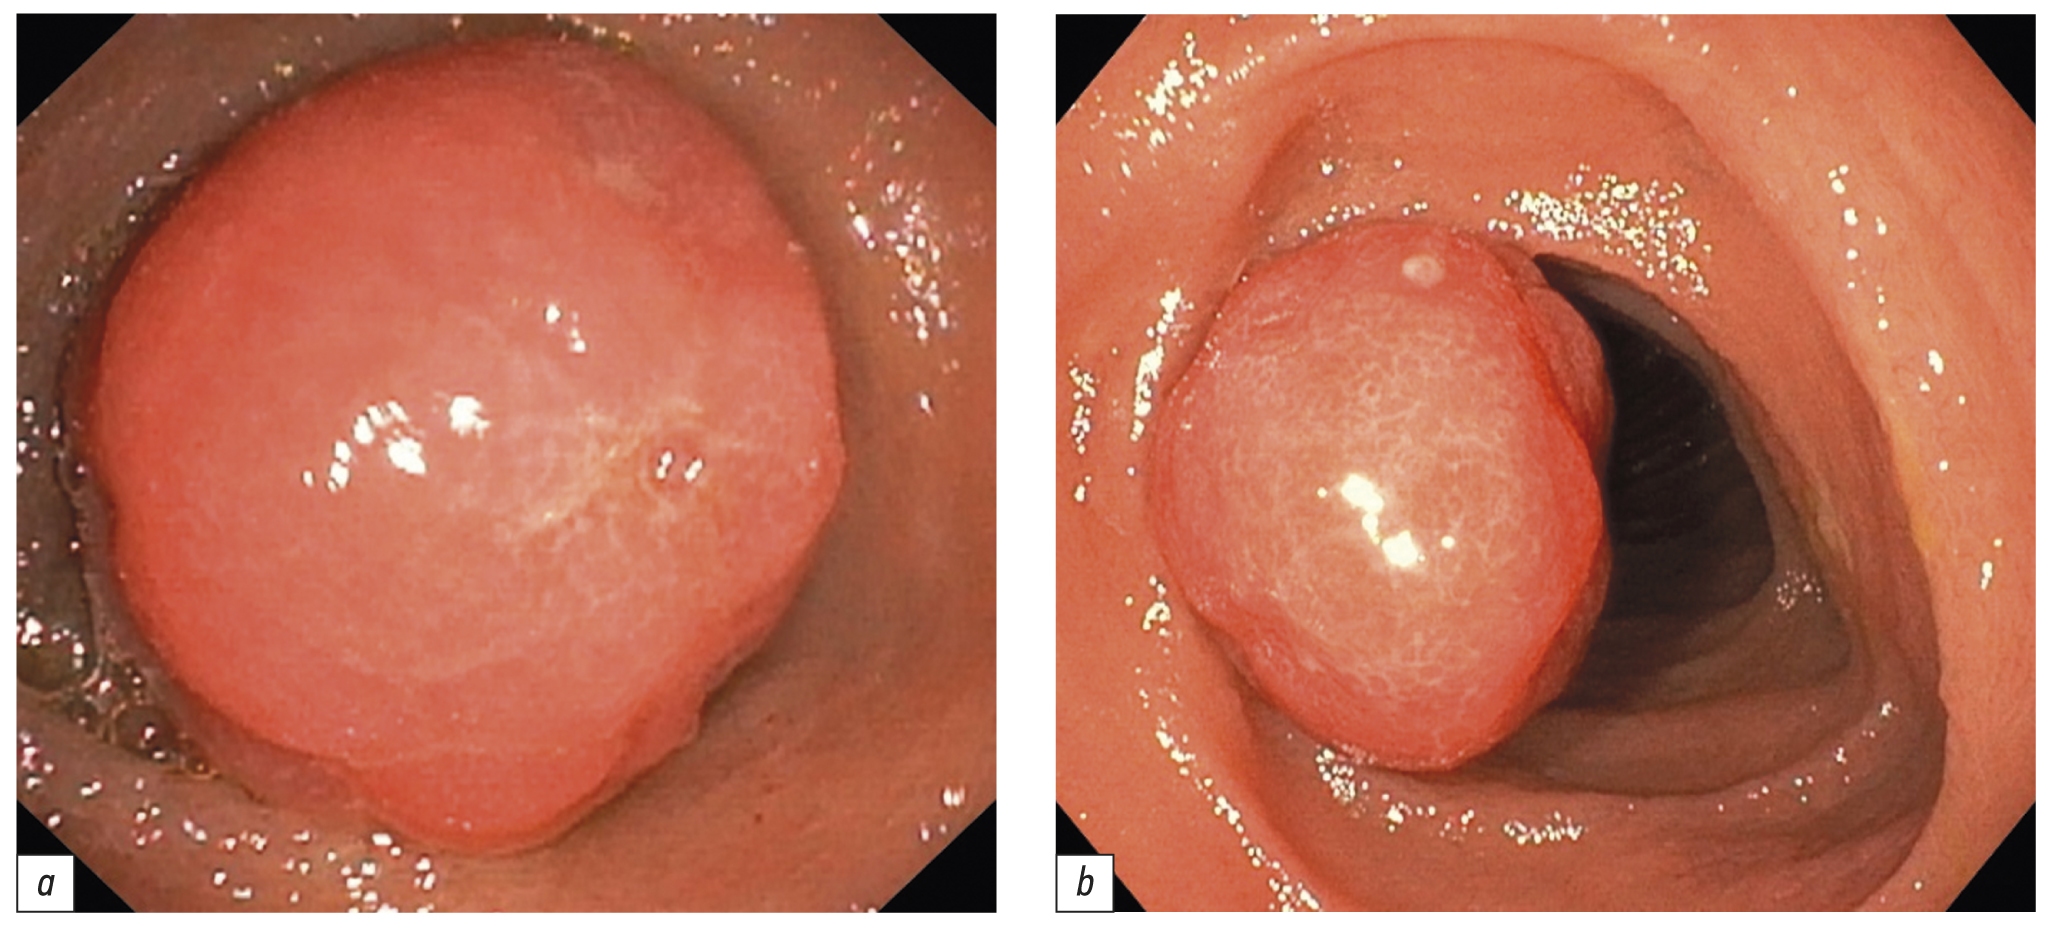

Поскольку в день операции у ребёнка был отмечен очередной эпизод мелены, для исключения поражений Дьелафуа, а также для осмотра тощей кишки на уровне расправленного тонкокишечного инвагината (30–40 см от связки Трейтца) интраоперационным консилиумом принято решение выполнить третье эндоскопическое исследование верхних отделов ЖКТ. В положении ребёнка на левом боку под СО2-инсуффляцией с применением ручного пособия тонкий видеогастроскоп заведён в тощую кишку, где на расстоянии около 40 см от пилорического канала было обнаружено эпителиальное новообразование шаровидной формы размерами 15×17 мм на короткой широкой ножке толщиной около 6 мм (тип 0-Ip по Парижской классификации эпителиальных новообразований) (рис. 6). Поверхность полипа гиперемирована, покрыта единичными округлыми эрозиями с налётом фибрина. Новообразование легко смещалось в просвете кишки при помощи инструментальной пальпации. С целью расширения возможностей инструментария тонкий видеогастроскоп заменён на аппарат стандартного диаметра с рабочим каналом 2,8 мм, который с техническими трудностями, обусловленными малым диаметром просвета ЖКТ у ребёнка, был проведён к новообразованию. Первым этапом с помощью эндоскопического инъектора выполнено введение в подслизистый слой физиологического раствора с индигокарминовым красителем в основание полипа с целью создания гидравлической подушки между слизистой и мышечной оболочками стенки кишки (рис. 7). Отмечен умеренный лифтинг новообразования. Эндоскопической серповидной петлёй Olympus Snare Master 25 мм выполнен захват полиповидного образования в пределах неизменённых тканей и затягивание петли на ножке образования (рис. 8). Выполнено удаление полипа в пределах неизменённых тканей в смешанном режиме коагуляции-резания (электрохирургический блок Olympus) методикой эндоскопической резекции слизистой оболочки. При осмотре после резекции признаков резидуальных тканей новообразования и глубокого повреждения стенки кишки не определялось. Отмечено подтекание крови из ложа удалённого образования. Выполнен гемостаз и сведение краёв дефекта слизистой при помощи трех эндоскопических клипс (рис. 9). Полип извлечён при помощи эндоскопического сачка из просвета ЖКТ и направлен на морфологическое исследование (рис. 10, 11).

Рис. 6. Полип тощей кишки: a — осмотр тонким видеогастроскопом, b — осмотр стандартным видеогастроскопом

Fig. 6. A jejunal polyp: a — image from the thin endoscope, b — image from the standard endoscope